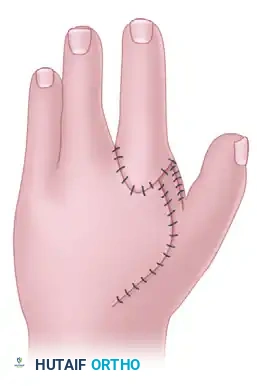

3. Closure

- The skin flaps are meticulously inset. The Miura and Komada design often allows for a primary closure that naturally deepens the first web space while closing the central defect.

Final appearance of the hand after wound closure, demonstrating a restored transverse arch and a deepened first web space.